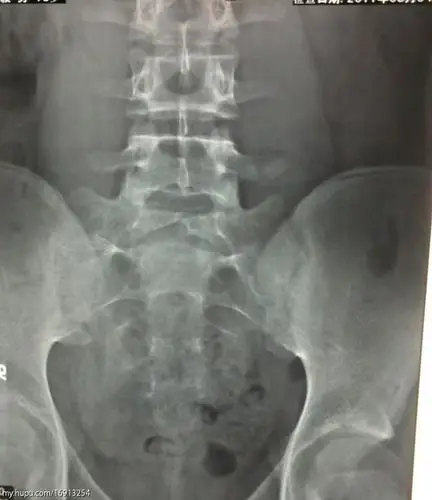

温故知新脊柱裂的分型